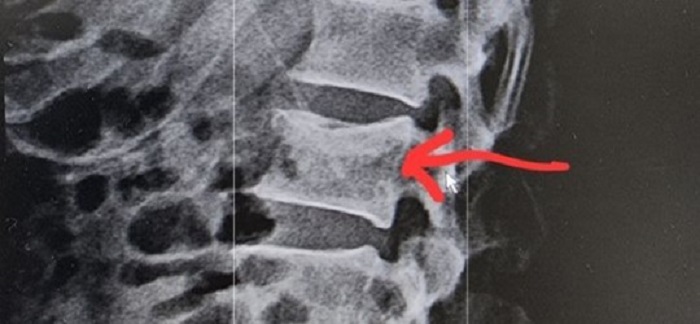

사례 2. 60대 남성 경추5,6,7번 골절 (수술 有)

☞ 척추 심한 운동장해 지급률 40%!!